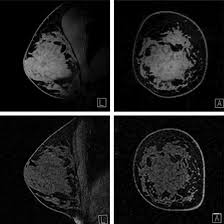

MRI Mammography (or Breast MRI) is a diagnostic study that utilizes a powerful magnetic field, radio waves, and digital signal processing to produce relatively high contrast pictures of the breast tissue. It is most useful for patients with high risk of developing breast cancer or patients with dense breast tissue, in which cases screen films may not detect small abnormalities. MRI Spectroscopy (MRS), on the contrary, performs beyond structural imaging. It evaluates the biochemical content of the kind of tissue, and from the change in the metabolism of this particular kind of tissue it may be able to identify the presence of cancer before the latter manifests structural deformities. It enables the early diagnosis of tumors and how breast cancer is likely to be in treatment.

MRI Mammography, or Breast MRI, is an advanced imaging technology used to create detailed pictures of the breast. This imaging technique differs from other mammograms in that they do not rely on X-rays but on powerful magnets and radio waves to make a high-resolution image of the breast. This creates a deeper understanding of breast health and can even detect abnormalities like tumors that might not be evident in other types of images.